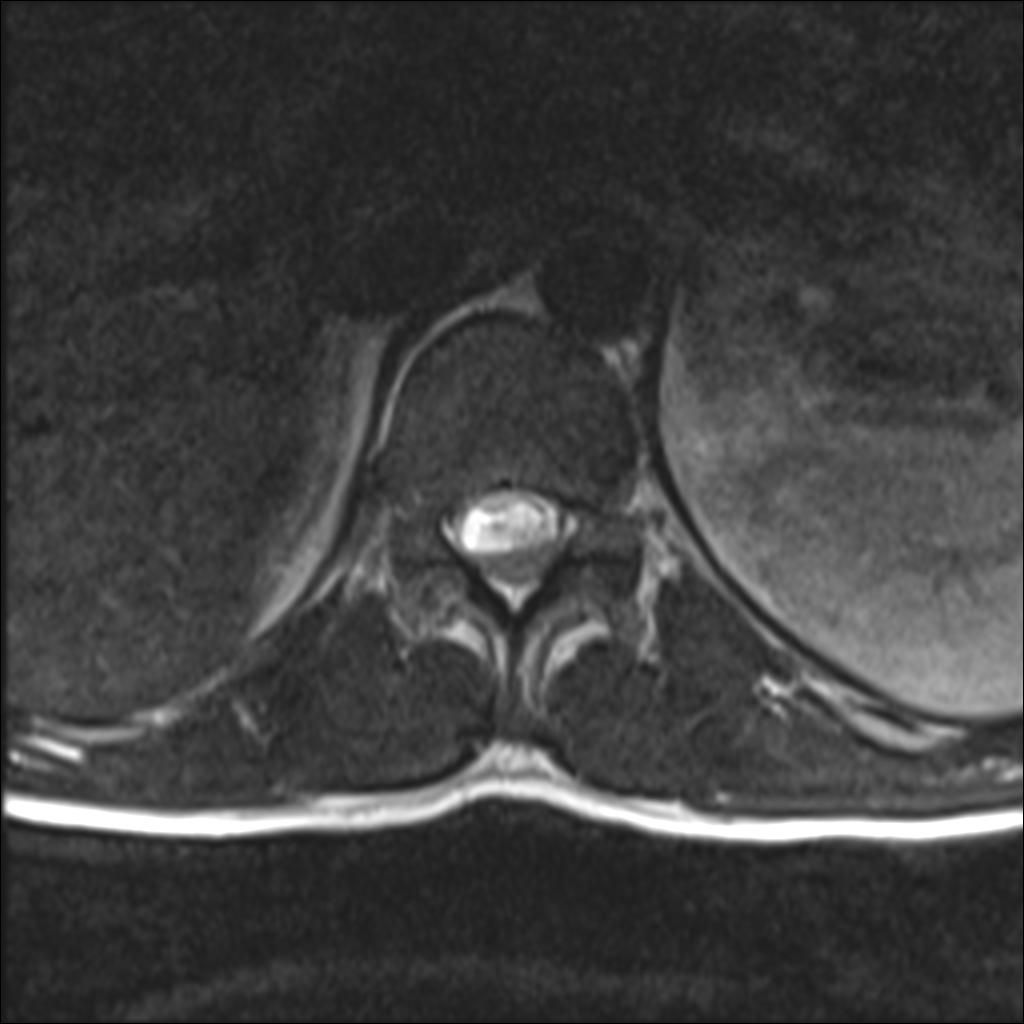

Can you diagnose this patient with low back pain, right lower extremity paraesthesias, and incontinence?

Case History: 40-year-old man with low back pain, right lower extremity paraesthesias, and incontinence. He presents 10 days later with worsening pain.

What is your diagnosis?